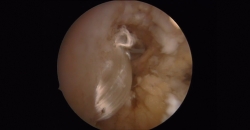

En las artroscopias, en todos los casos se observó una rotura completa del LPAA con presencia de fibras del ligamento en diferentes fases degenerativas.

Figura 8. Plastia una vez realizado el bloqueo a nivel del astrágalo. Resultado final.